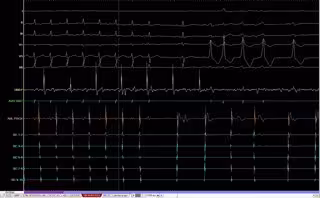

El grupo de investigación de Ingeniería Electrónica, Biomédica y de Telecomunicaciones de la Universidad de Castilla-La Mancha (UCLM), junto a investigadores de la Universidad Politécnica de Valencia (UPV), han desarrollado un nuevo software que mejora la caracterización de arritmias cardiacas al poder ofrecer al cardiólgo información "desconocida hasta el momento" sobre estas alteraciones.

Este estudio, que ha sido publicado en la revista científica 'Annals of Biomedical Engineering', explica que su incorporación a los equipos clínicos de electrofisiología cardiaca actuales permitiría obtener una señal "más nítida, definida y sin distorsiones en todo tipo de arritmias", fundamentalmente la fibrilación auricular, la más común en la actualidad, según ha informado la UCLM en una nota de prensa.

En este trabajo, los investigadores realizaron un estudio en el que demostraron cómo los sistemas actuales de electrofisiología cardiaca realizan un tratamiento de la señal que puede alterar sustancialmente la morfología de los registros obtenidos.

"El problema reside en que las técnicas de filtrado que utilizan pueden ser inadecuadas, por lo que, si dichos registros son empleados posteriormente como base para la caracterización electrofisiológica del paciente, puede producir errores significativos en la estimación de parámetros esenciales sobre su estado arrítmico", explica Rieta.

El software desarrollado por los investigadores de UCLM y de la UPV evita esos errores. De hecho, permite reducir hasta en un 40 por ciento la distorsión introducida por los sistemas convencionales de adquisición electrofisiológica.